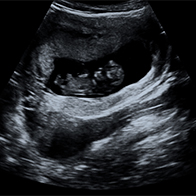

There's no way to prevent ectopic pregnancies, although regular STI testing can prevent the kind of fallopian tube scarring that facilitates these conditions. The best way to stay safe is to follow up a positive pregnancy test with a visit to your healthcare provider. An ultrasound can confirm whether the placenta has taken root inside your uterus or elsewhere.